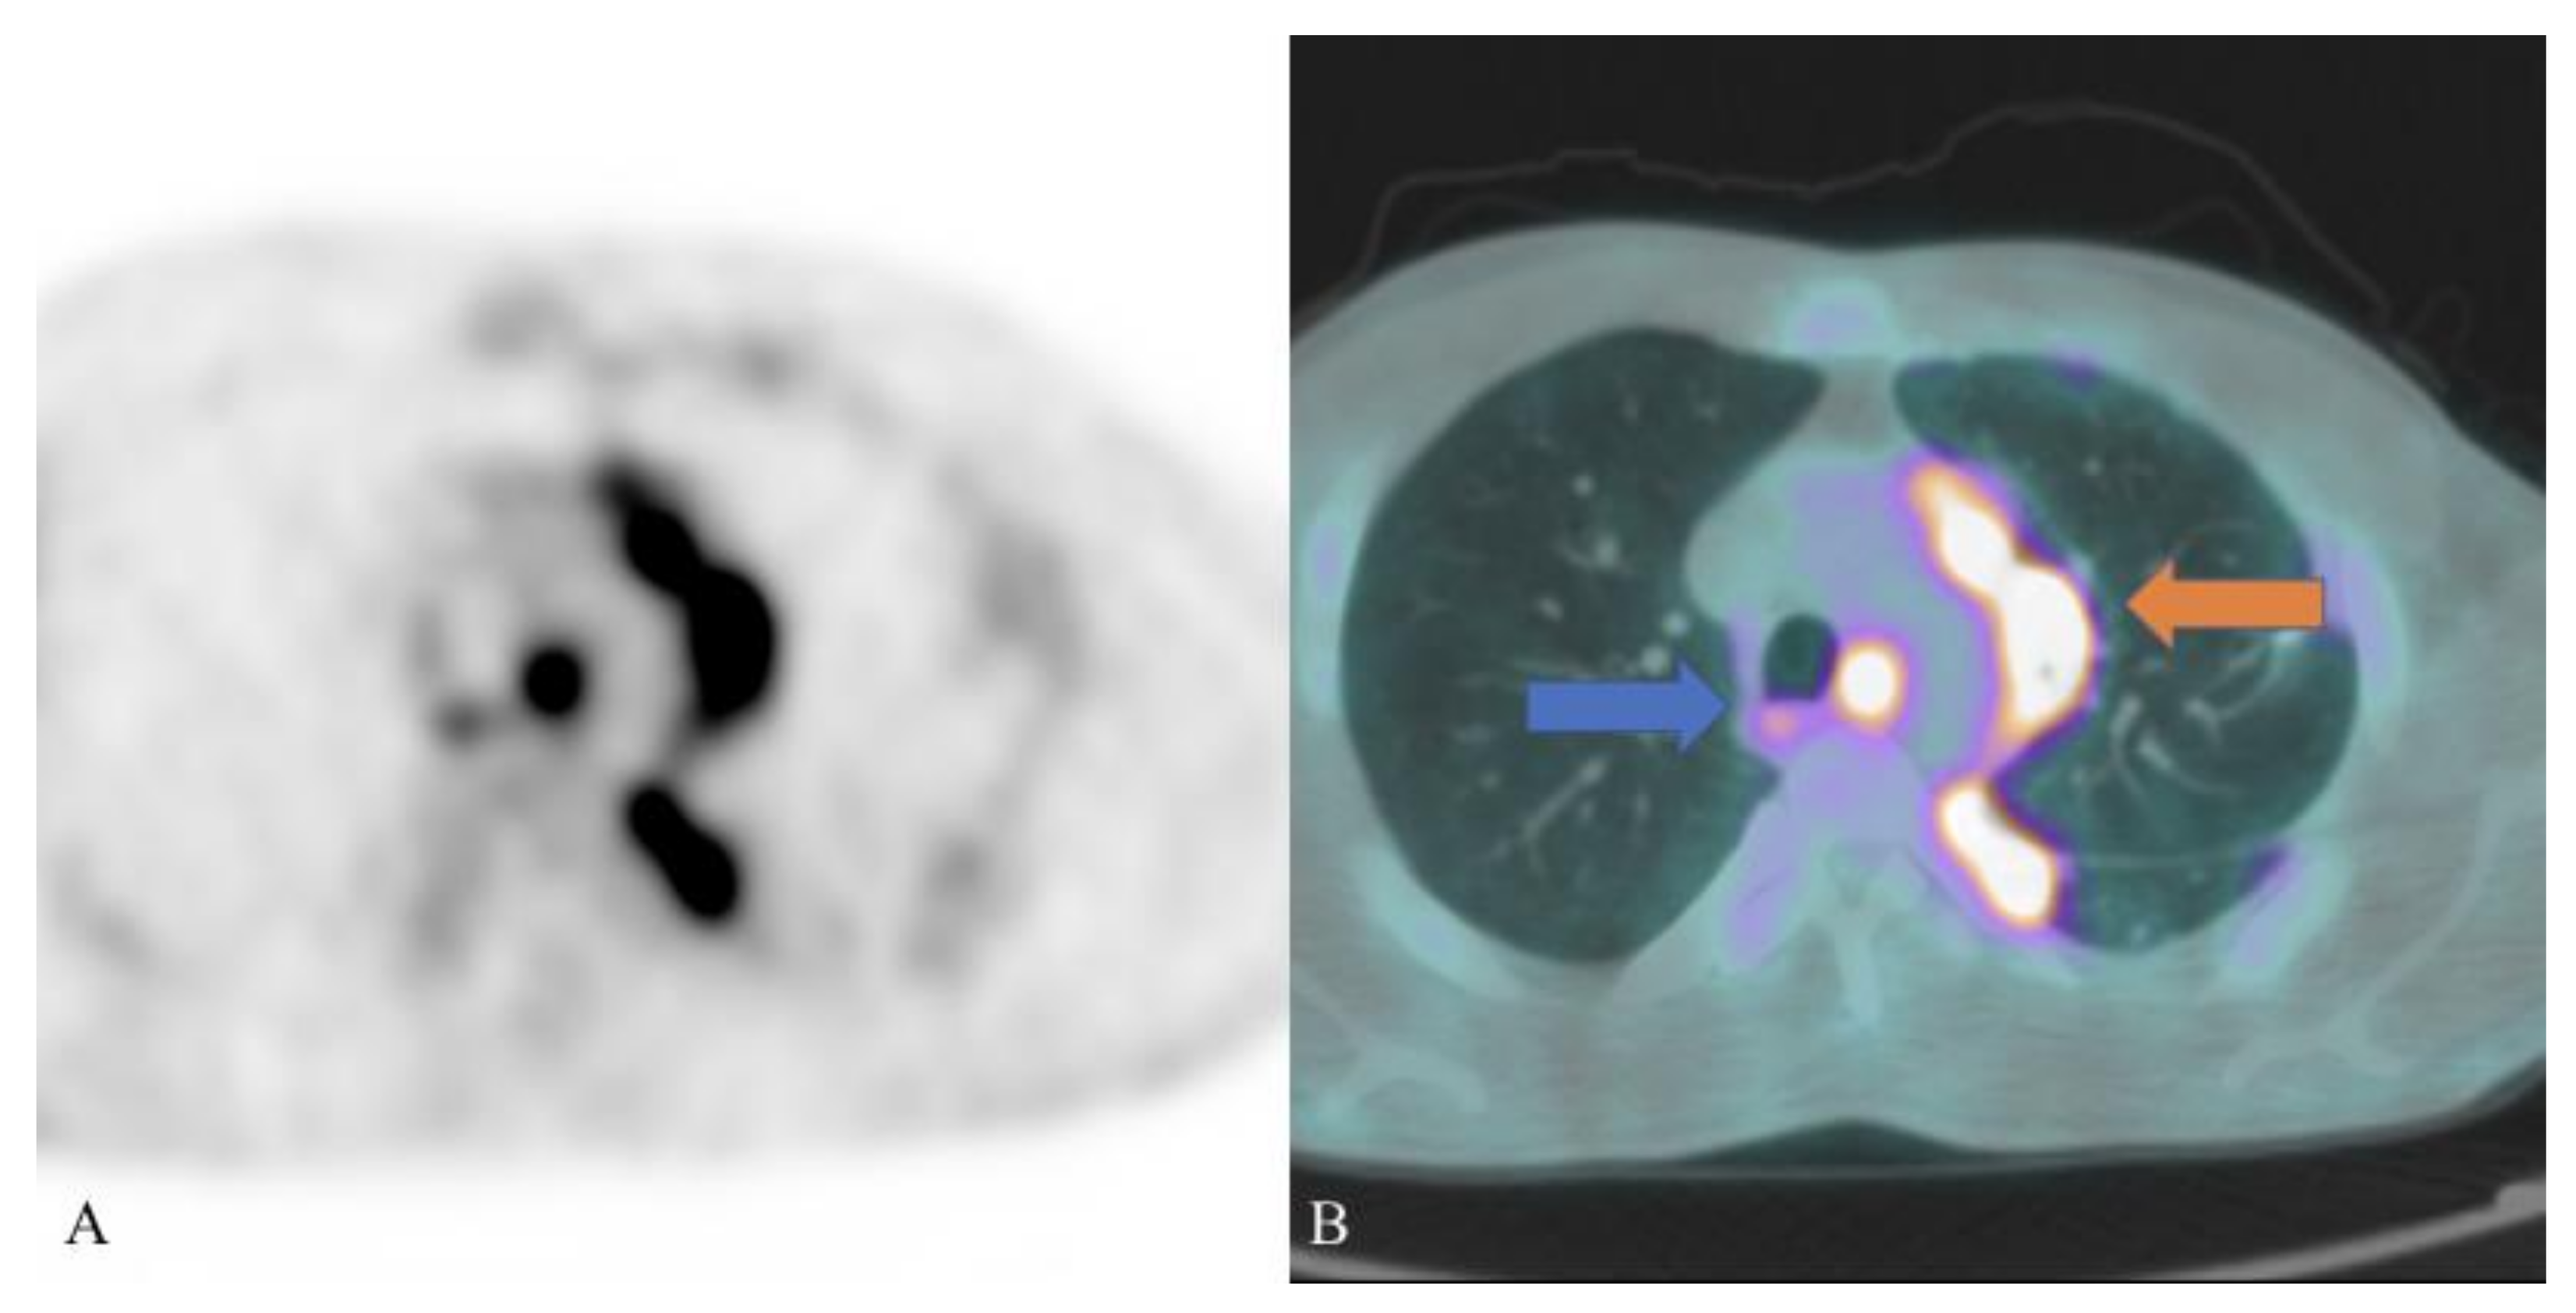

- Cimini, A.; Ricci, M.; Chiaravalloti, A.; Crocco, A.; Russo, F.; Schillaci, O. A rare case of pulmonary schistosomiasis: 18F-fluorodeoxyglucose positron emission tomography/computed tomography findings. Indian J. Nucl. Med. 2020, 35, 336–338. [Google Scholar] [CrossRef] [PubMed]